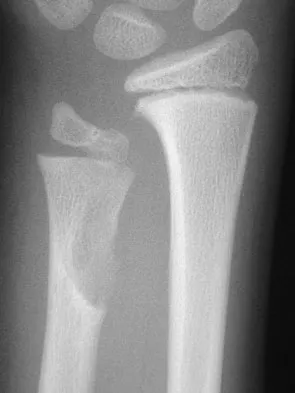

Figure 31 shows the AP and lateral radiographs of the elbow of a 56-year-old man with chronic polyarticular rheumatoid arthritis. His function continues to be limited by pain with activities of daily living. Examination shows that his total arc of motion is 110 degrees. Nonsurgical management has failed to provide relief. Treatment should now consist of

A semiconstrained prosthesis can provide excellent results in carefully selected patients. Because the radiographs show extensive joint destruction with loss of the capitellum and trochlea, a capitellocondylar total elbow (unconstrained) prosthesis is contraindicated. Elbow fusion is poorly accepted, and the radiographs show too much articular destruction for a radial head excision, synovectomy, or interposition arthroplasty to be effective. Ewald FC, Simmons ED Jr, Sullivan JA, et al: Capitellocondylar total elbow replacement in rheumatoid arthritis: Long-term results. J Bone Joint Surg Am 1993;75:498-507.